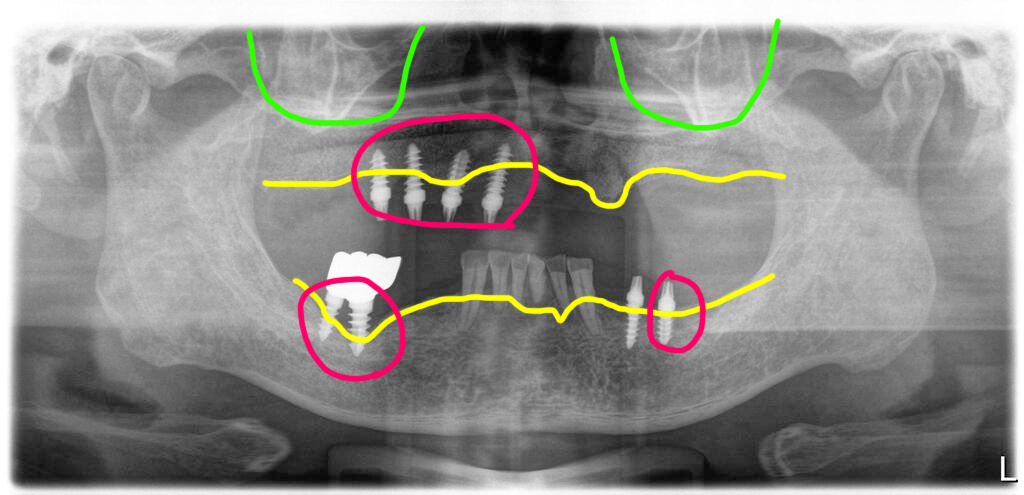

해당 병원이 없어져서 치료를 고민하다가 저희 병원에 방문하게 되셨습니다. 아래는 어금니 부분에 임플란트가 심겨져 있었는데 그 임플란트도 임플란트 주위염이 진행되어 있었습니다.

임플란트주위염으로

뼈가 놓은 이전에 심은 임플란트들

이미 보철에 딸려 나온 임플란트도 있었고, 입 안에 남아있는 임플란트들도 임플란트주위염으로 뼈가 녹아 있어서 장기적으로 사용이 힘들다고 판단하여 제거하고 다시 임플란트를 심기로 했습니다. 다행히 가용골이 있어서 임플란트 제거와 함께 식립을 하기로 했어요.

상악은 임플란트주위염으로 뼈가 녹은 임플란트 4개를 제거한 후 남아있는 뼈에 10개의 임플란트를 식립했습니다.

하악 우측 어금니 부위는 염증이 심할 뿐 아니라 신경관과의 거리가 너무 가까워 그부분은 식립을 하지 않았어요. 임플란트를 심지 않은 부분은 캔틸레버로 처리했어요. 하악좌측에 이전에 심은 임플란트 중 한개는 상태가 괜찮아 남겼구요.